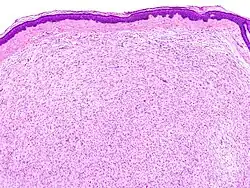

Neurofibrom der Haut, mikroskopisches Bild

Neurofibrome sind Nerventumore, die innerhalb des Nervs gut abgrenzbare oder außerhalb des Nervs diffuse Strukturen ausbilden. Sie bestehen aus neoplastischen Schwann-Zellen, Fibroblasten und perineuralen Zellen, die in eine Matrix aus Kollagenfasern eingebettet sind. Sie werden auf der WHO-Skala von I-IV mit der Stufe I klassifiziert. Vom Schwannom unterscheiden sie sich durch einen höheren Gehalt an bindegewebiger Substanz und dadurch, dass sie operativ nicht von den Nerven getrennt werden können und diese in der Regel geopfert werden müssen.